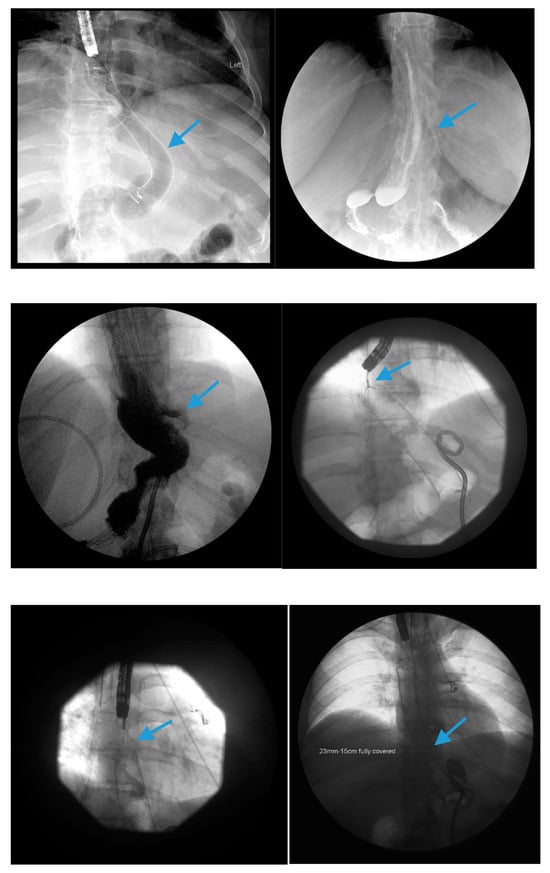

Scheme 4.

Fluoroscopic image demonstrates the placement of a 23 mm × 15 cm partially-covered esophageal self-expanding metal stent from the distal esophagus to the pylorus (arrow, top left) for the treatment of a leak in a patient following sleeve gastrectomy. Contrast injected endoscopically (arrows, top right and middle left) reveals a small, persistent sleeve leak. The endoscopic removal of the stent was subsequently attempted using a grasper (arrows, middle right and bottom left), but the stent removal was unsuccessful due to tissue ingrowth. A 23 mm × 15 cm, fully-covered, esophageal self-expanding metal stent was placed within the prior stent (arrow, bottom right) to facilitate removal after pressure necrosis of the ingrown tissue.